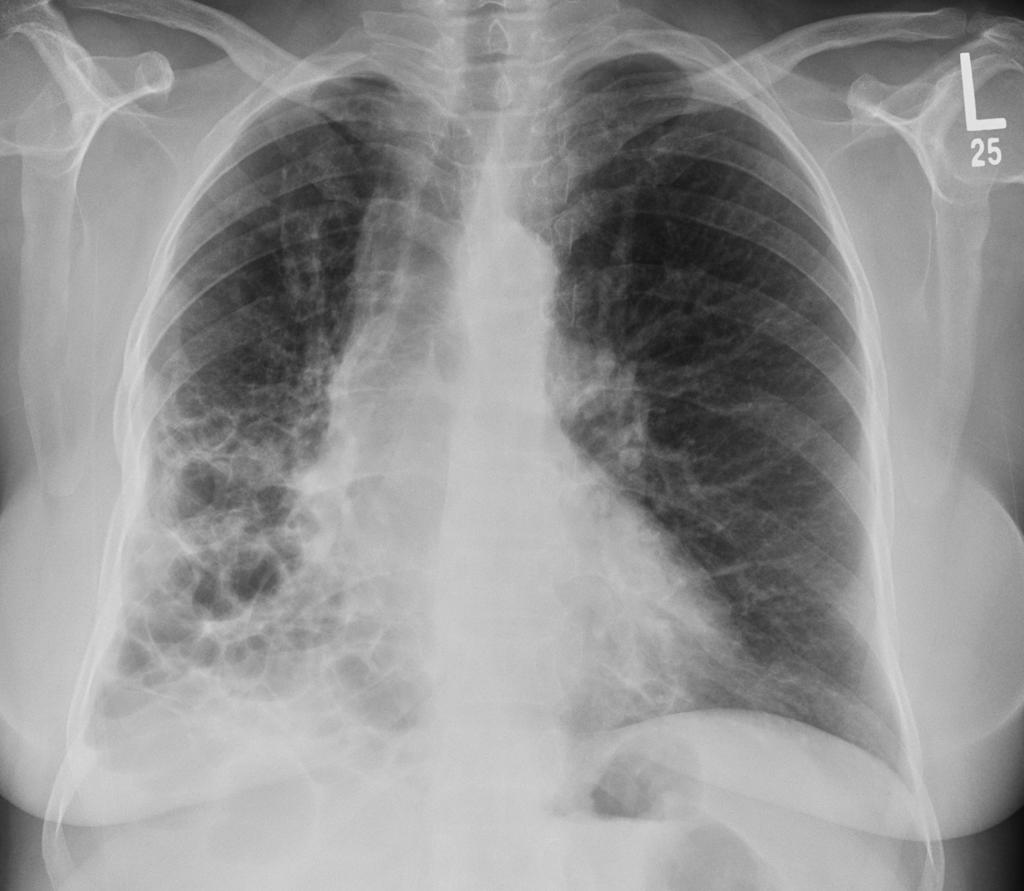

Fibrozni intersticijski proces pluća (fIPP) je bolest koju je teško kontrolisati sa ograničenim terapijskim mogućnostima i lošom prognozom. U trenutno objavljenom pregledu analiziraju se kriterijumi njegove progresije koji definišu prisustvo progresivne plućne fibroze (PPF), opisuje njihovu relativnu prevalenciju i prognostički značaj.

Veliki deo pacijenata sa fIPP, osim idiopatske plućne fibroze (IPF), doživljava progresiju bolesti uprkos početnom lečenju. Ovaj fenotip bolesti se naziva progresivna plućna fibroza (PPF). PPF je povezan sa visokim morbiditetom i mortalitetom. Većina pacijenata sa PPF ima dijagnozu fibroznog preosetljivog pneumonitisa (fHP), intersticijalnih plućnih procesa povezanih sa sistemskom bolešću vezivnog tkiva (SOP-IPP) ili idiopatske intersticijalne pneumonije (IIP) koja nije IPF (uključujući fibrozirajuću nespecifičnu intersticijalnu intersticijalnu pneumoniju i upalu pluća). proces). Na osnovu retrospektivnih podataka procenjeno je da je procenat pacijenata sa PPF-om koji padaju u fibrotični ne-IPF IPP posle 24 meseca van fibrozne sarkoidoze 30%. Ali prevalencija PPF varira u skladu sa definicijom progresije.